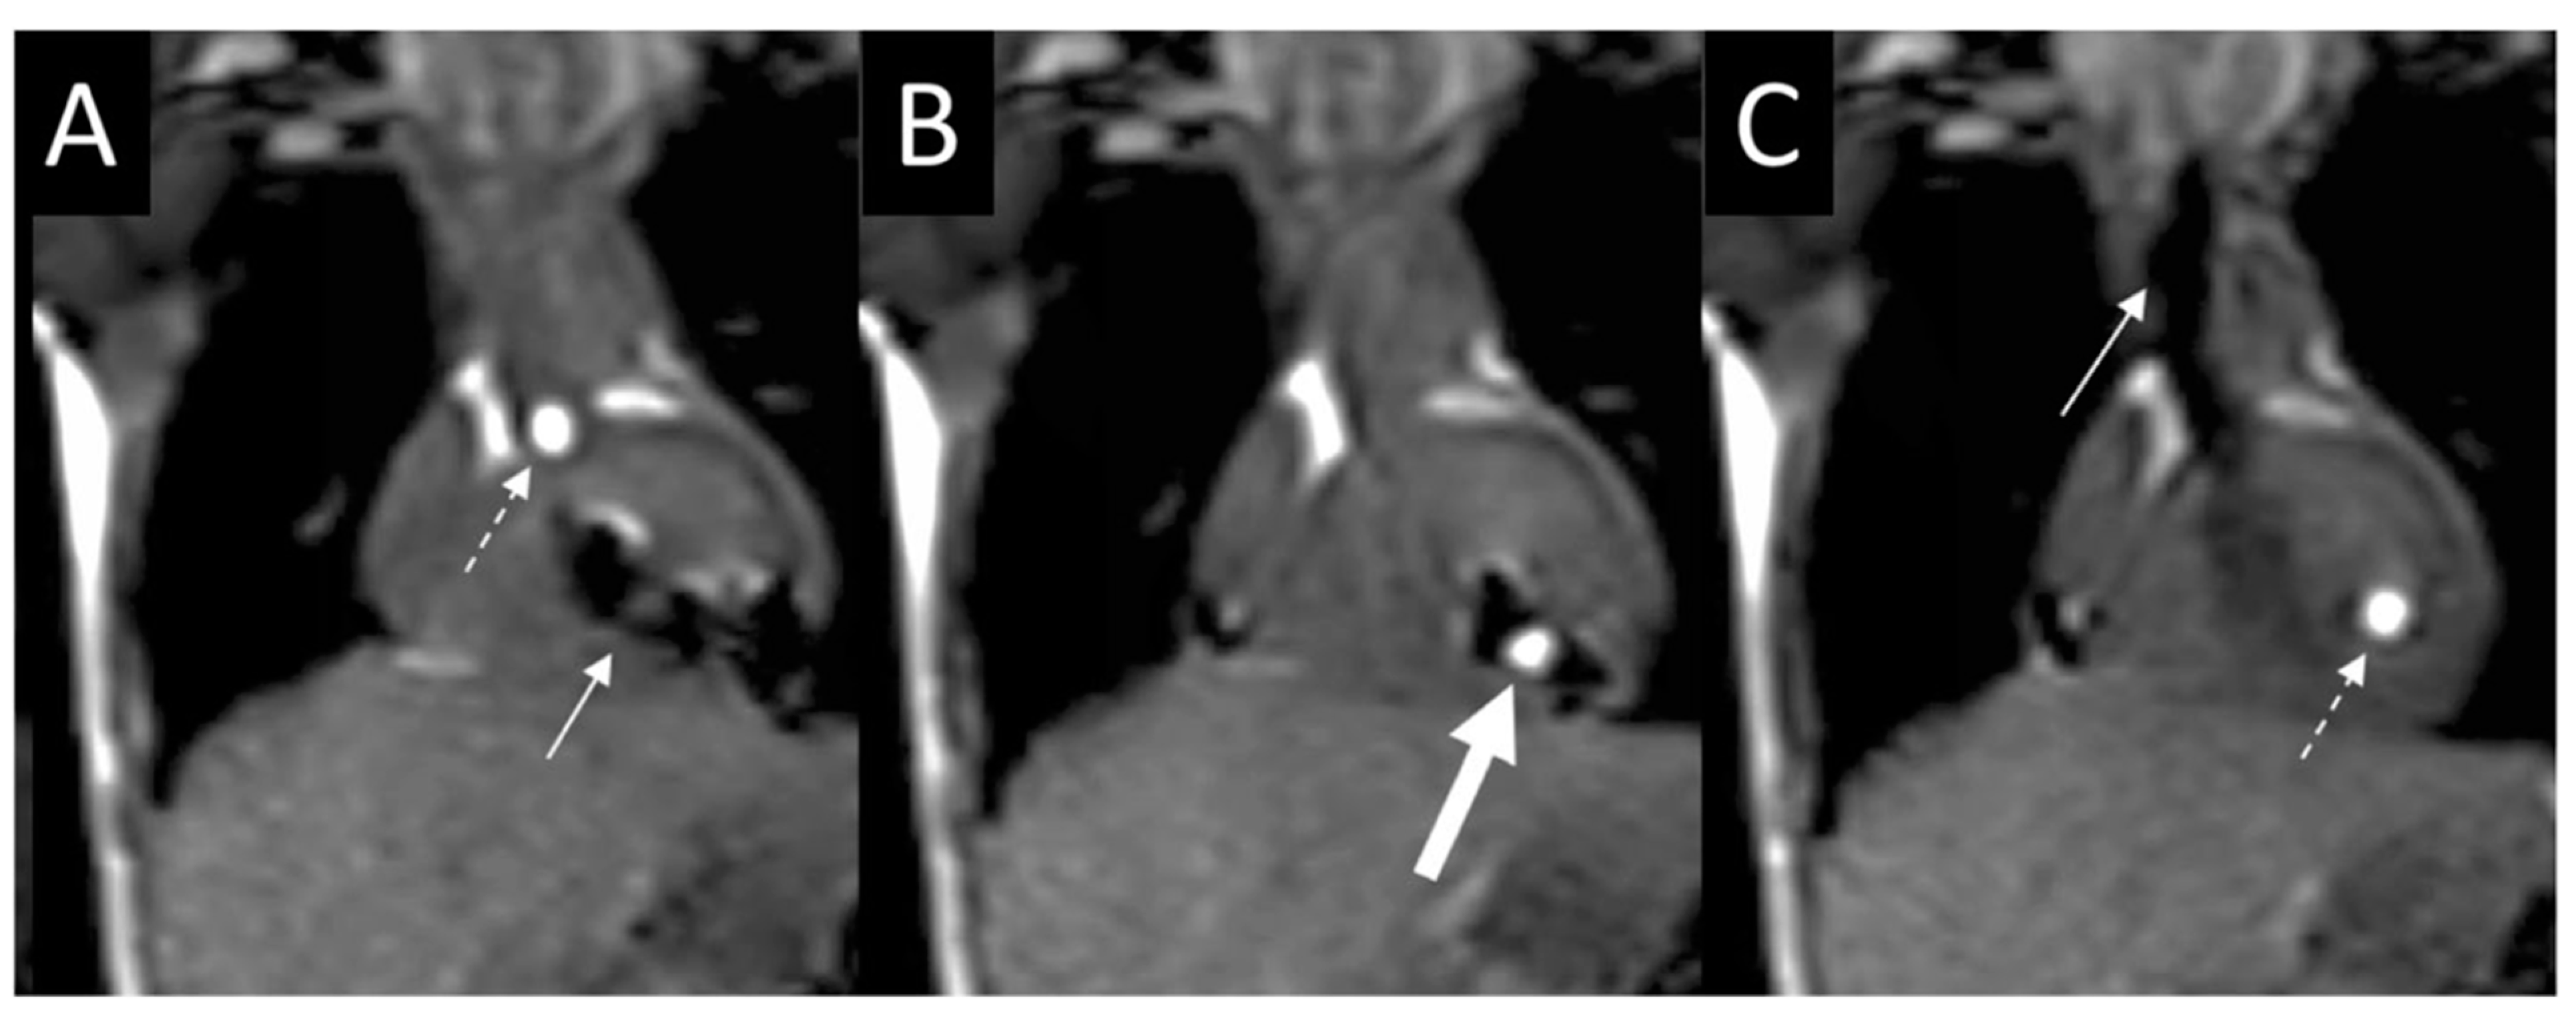

2.3. Percutaneous Pulmonary Valve Placement